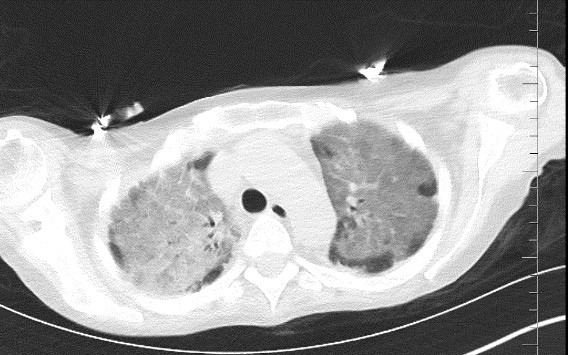

Serum galactomannan antigen test taken on the 2nd day of ICU hospitalization was found 0.65 S/CO but not was considered significant. Thorax CT scan performed on 18/01/24 revealed consolidation areas especially in the upper lobes and diffuse infiltration areas which were evaluated in favor of viral pneumonia in the foreground, and ARDS should be considered in the differential diagnosis (Figure 1).